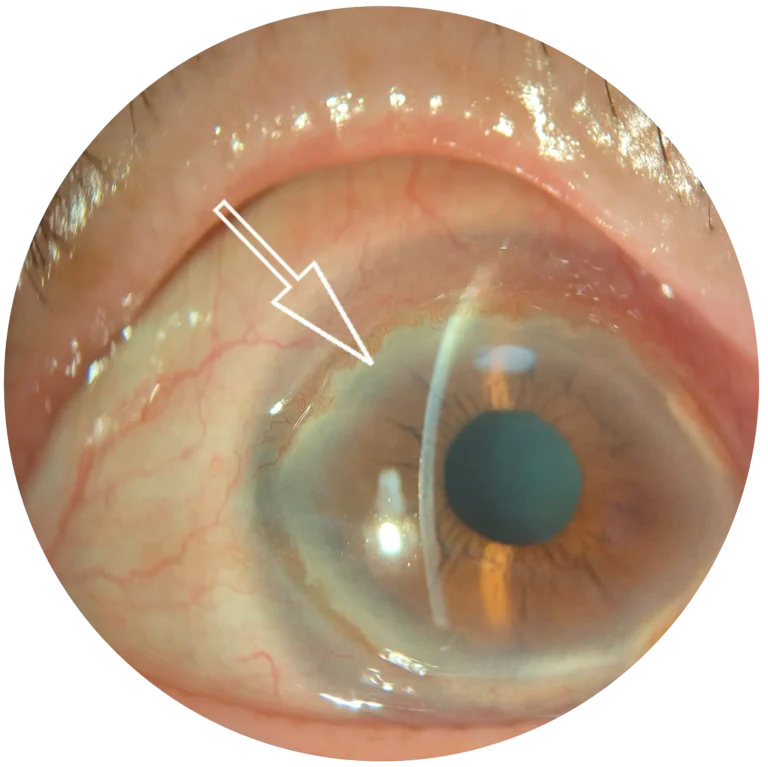

“We only treated two eyes, but it was the first time a Terrien could be stopped and partially reversed,” Farhad Hafezi, MD, PhD, OSN Europe Edition Board Member, said in a telephone interview with Ocular Surgery News